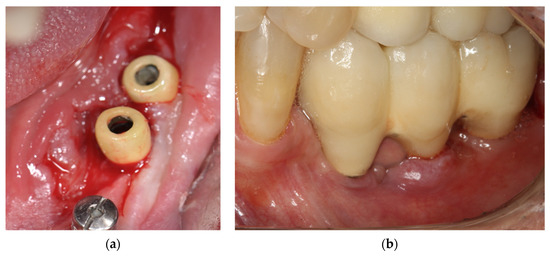

3.8. Case Report

- Borgonovo, A.E.; Censi, R.; Vavassori, V.; Savio, M.; Re, D. A Possible Relationship between Peri-Implantitis, Titanium Hypersensitivity, and External Tooth Resorption: Metal-Free Alternative to Titanium Implants. Case Rep. Dent. 2021, 2021, 8879988. [Google Scholar] [PubMed]

| Borgonovo et al. [34] | Swelling and redness in peri-implant tissues and bleeding and a probing depth of 6 mm, bucally and 5 mm lingually, high mucosa sensitivity and implant exposure. | a bony defect with a crater-like shape around first molar implant and cervical decay on teeth and vertical bone loss involved the new implants and the process of external resorption affected the teeth up to the canine | Removal of the titanium implant, after nine months, when allergic symptoms disappeared, five one-piece zirconia implants were inserted, four in the anterior jaw and 1 in the right molar region | Biopsy was performed by taking a sample of cortical and medullary bone to check for bone disorder. the result did not show any kind of bone lesion or disease. | A standard blood tests revealed an increased number of eosinophils. MELISA (Memory Lymphocyte Immunostimulation Assay) test was performed and confirmed titanium hypersensitivity. The bacterial culture was negative. | During the follow-up period, the patient did not refer to any symptoms of peri-implantitis or other problems, and after 18 months from surgery, the clinical-radiographic exams showed the success of the metal-free implant prosthetic rehabilitation. | |